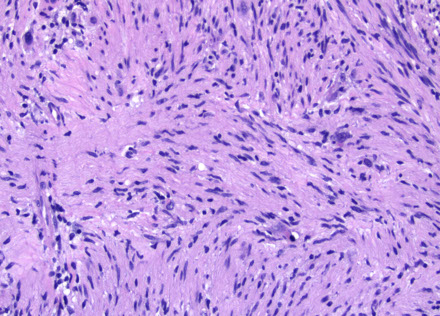

Micro: fascicular monomorphic serpentine spindle cells c large vascular spaces with geographic necrosis c palisading around edges

- lots o mits

MPNST